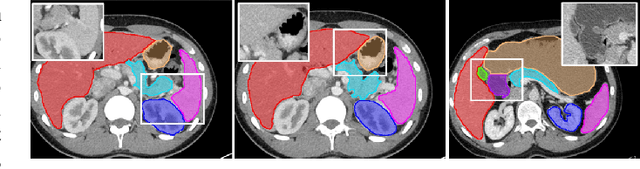

Abstract:Automatic segmentation of abdominal organs in computed tomography (CT) images can support radiation therapy and image-guided surgery workflows. Developing of such automatic solutions remains challenging mainly owing to complex organ interactions and blurry boundaries in CT images. To address these issues, we focus on effective spatial context modeling and explicit edge segmentation priors. Accordingly, we propose a 3D network with four main components trained end-to-end including shared encoder, edge detector, decoder with edge skip-connections (ESCs) and recurrent feature propagation head (RFP-Head). To capture wide-range spatial dependencies, the RFP-Head propagates and harvests local features through directed acyclic graphs (DAGs) formulated with recurrent connections in an efficient slice-wise manner, with regard to spatial arrangement of image units. To leverage edge information, the edge detector learns edge prior knowledge specifically tuned for semantic segmentation by exploiting intermediate features from the encoder with the edge supervision. The ESCs then aggregate the edge knowledge with multi-level decoder features to learn a hierarchy of discriminative features explicitly modeling complementarity between organs' interiors and edges for segmentation. We conduct extensive experiments on two challenging abdominal CT datasets with eight annotated organs. Experimental results show that the proposed network outperforms several state-of-the-art models, especially for the segmentation of small and complicated structures (gallbladder, esophagus, stomach, pancreas and duodenum). The code will be publicly available.